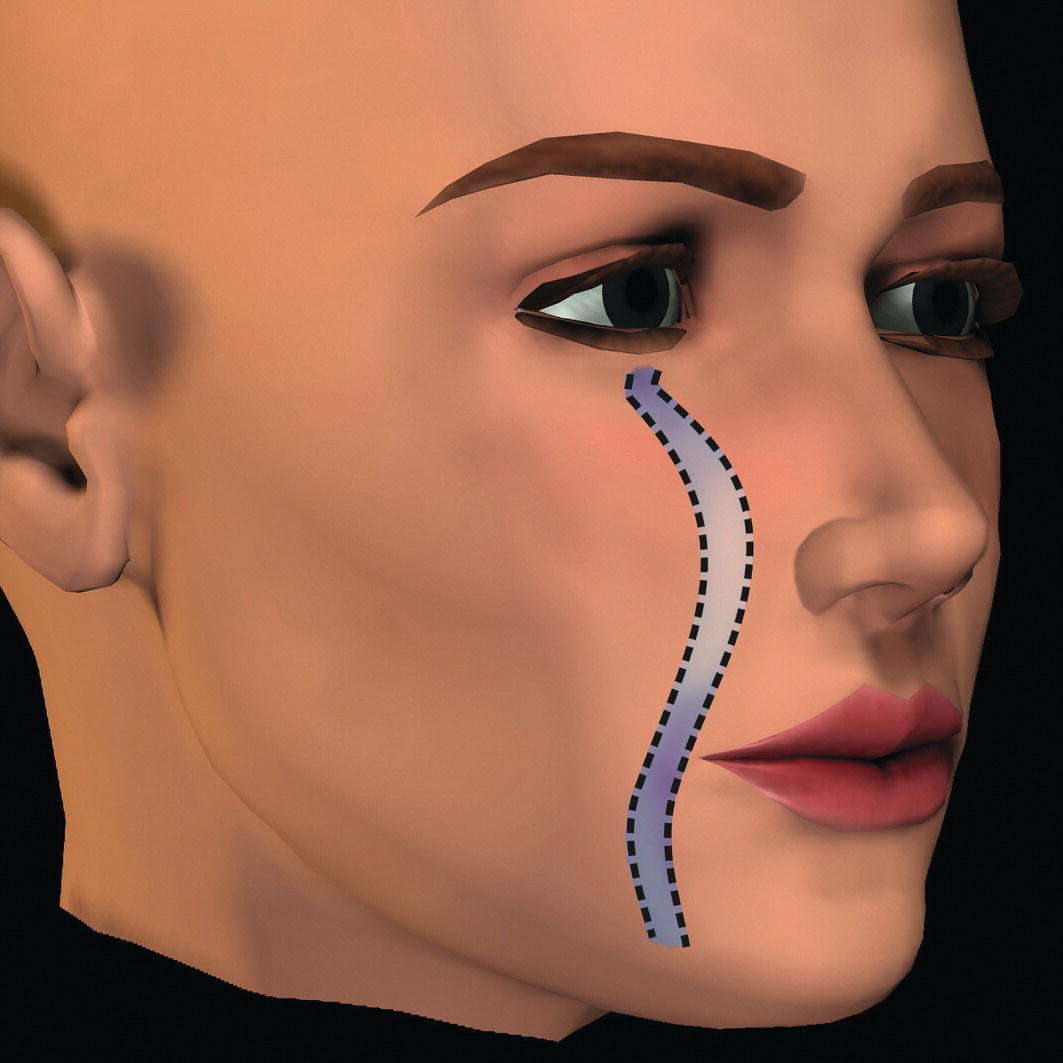

Parasagittal facial profile contour